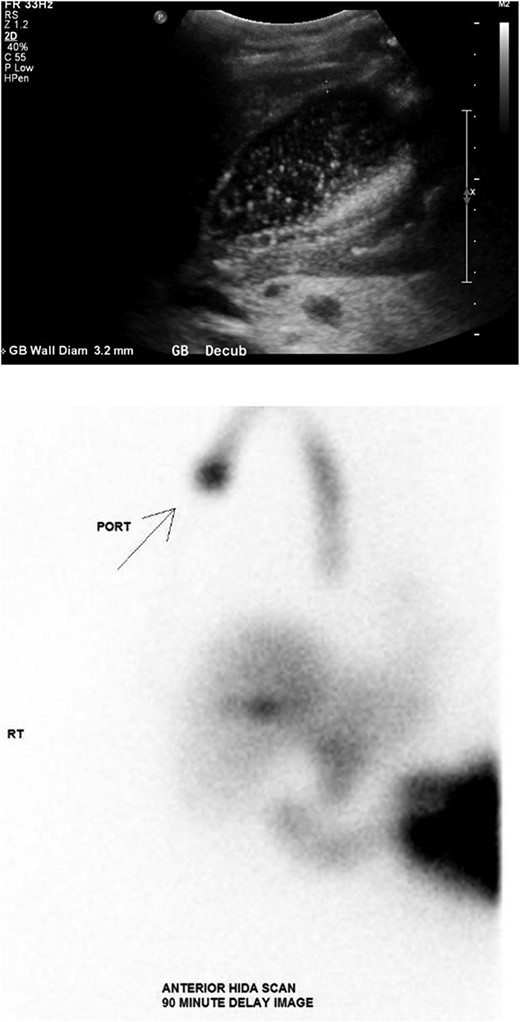

The patient was presented to the emergency department with a 4-week history of abdominal pain and intractable nausea and vomiting. She was vitally normal with normal liver function tests and no leukocytosis. Imaging revealed significant gallbladder distension, wall thickening, and pericholecystic inflammatory changes suggestive of acute cholecystitis (Fig. 1).

(Top) Ultrasound of the abdomen demonstrating distended gallbladder full of sludge with wall thickness of 3.2 mm. (Bottom) Nuclear medicine hepatobiliary scan demonstrating no gallbladder visualization after 90 minutes strongly supportive of acute cholecystitis.